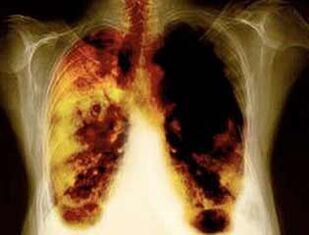

- Riduzione del rischio di sviluppare il cancro ai polmoni e molti altri tipi di cancro.

- Riduzione del rischio di sviluppo di determinate malattie polmonari (ad esempio malattie polmonari cronicamente ostruttive).

- Dopo 1-9 mesi, si verificano tosse e mancanza di respiro: zil (capelli piccoli) di solito iniziano a trattare il muco, per pulire i polmoni e ridurre il rischio di infezione.

- 10 anni dopo il fumo del 40%, la probabilità di cancro ai polmoni diminuisce del 40%.